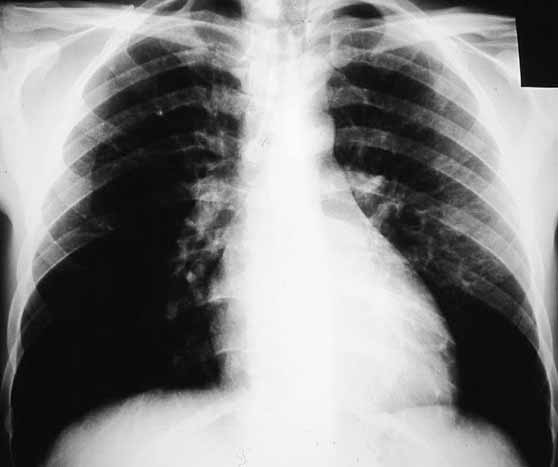

Figura 3. Radiografía simple de tórax en la que se aprecia cardiomegalia importante e infiltrados alveolares pulmonares bilaterales.